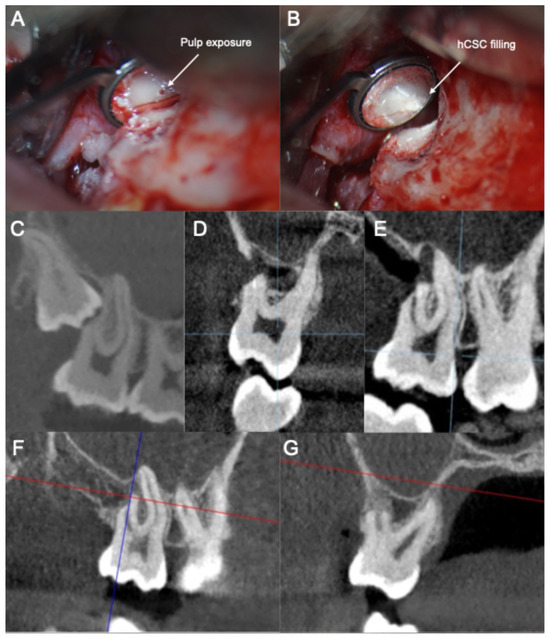

- (1)

- The smoothening of the ERR to allow for a clear visualization and access to the pulp exposure.

- (2)

- The creation of a retrograde cavity and partial pulpotomy of the pulp exposure.

- (3)

- The placement of a pulp capping agent in the cavity over the remaining vital pulp tissue.